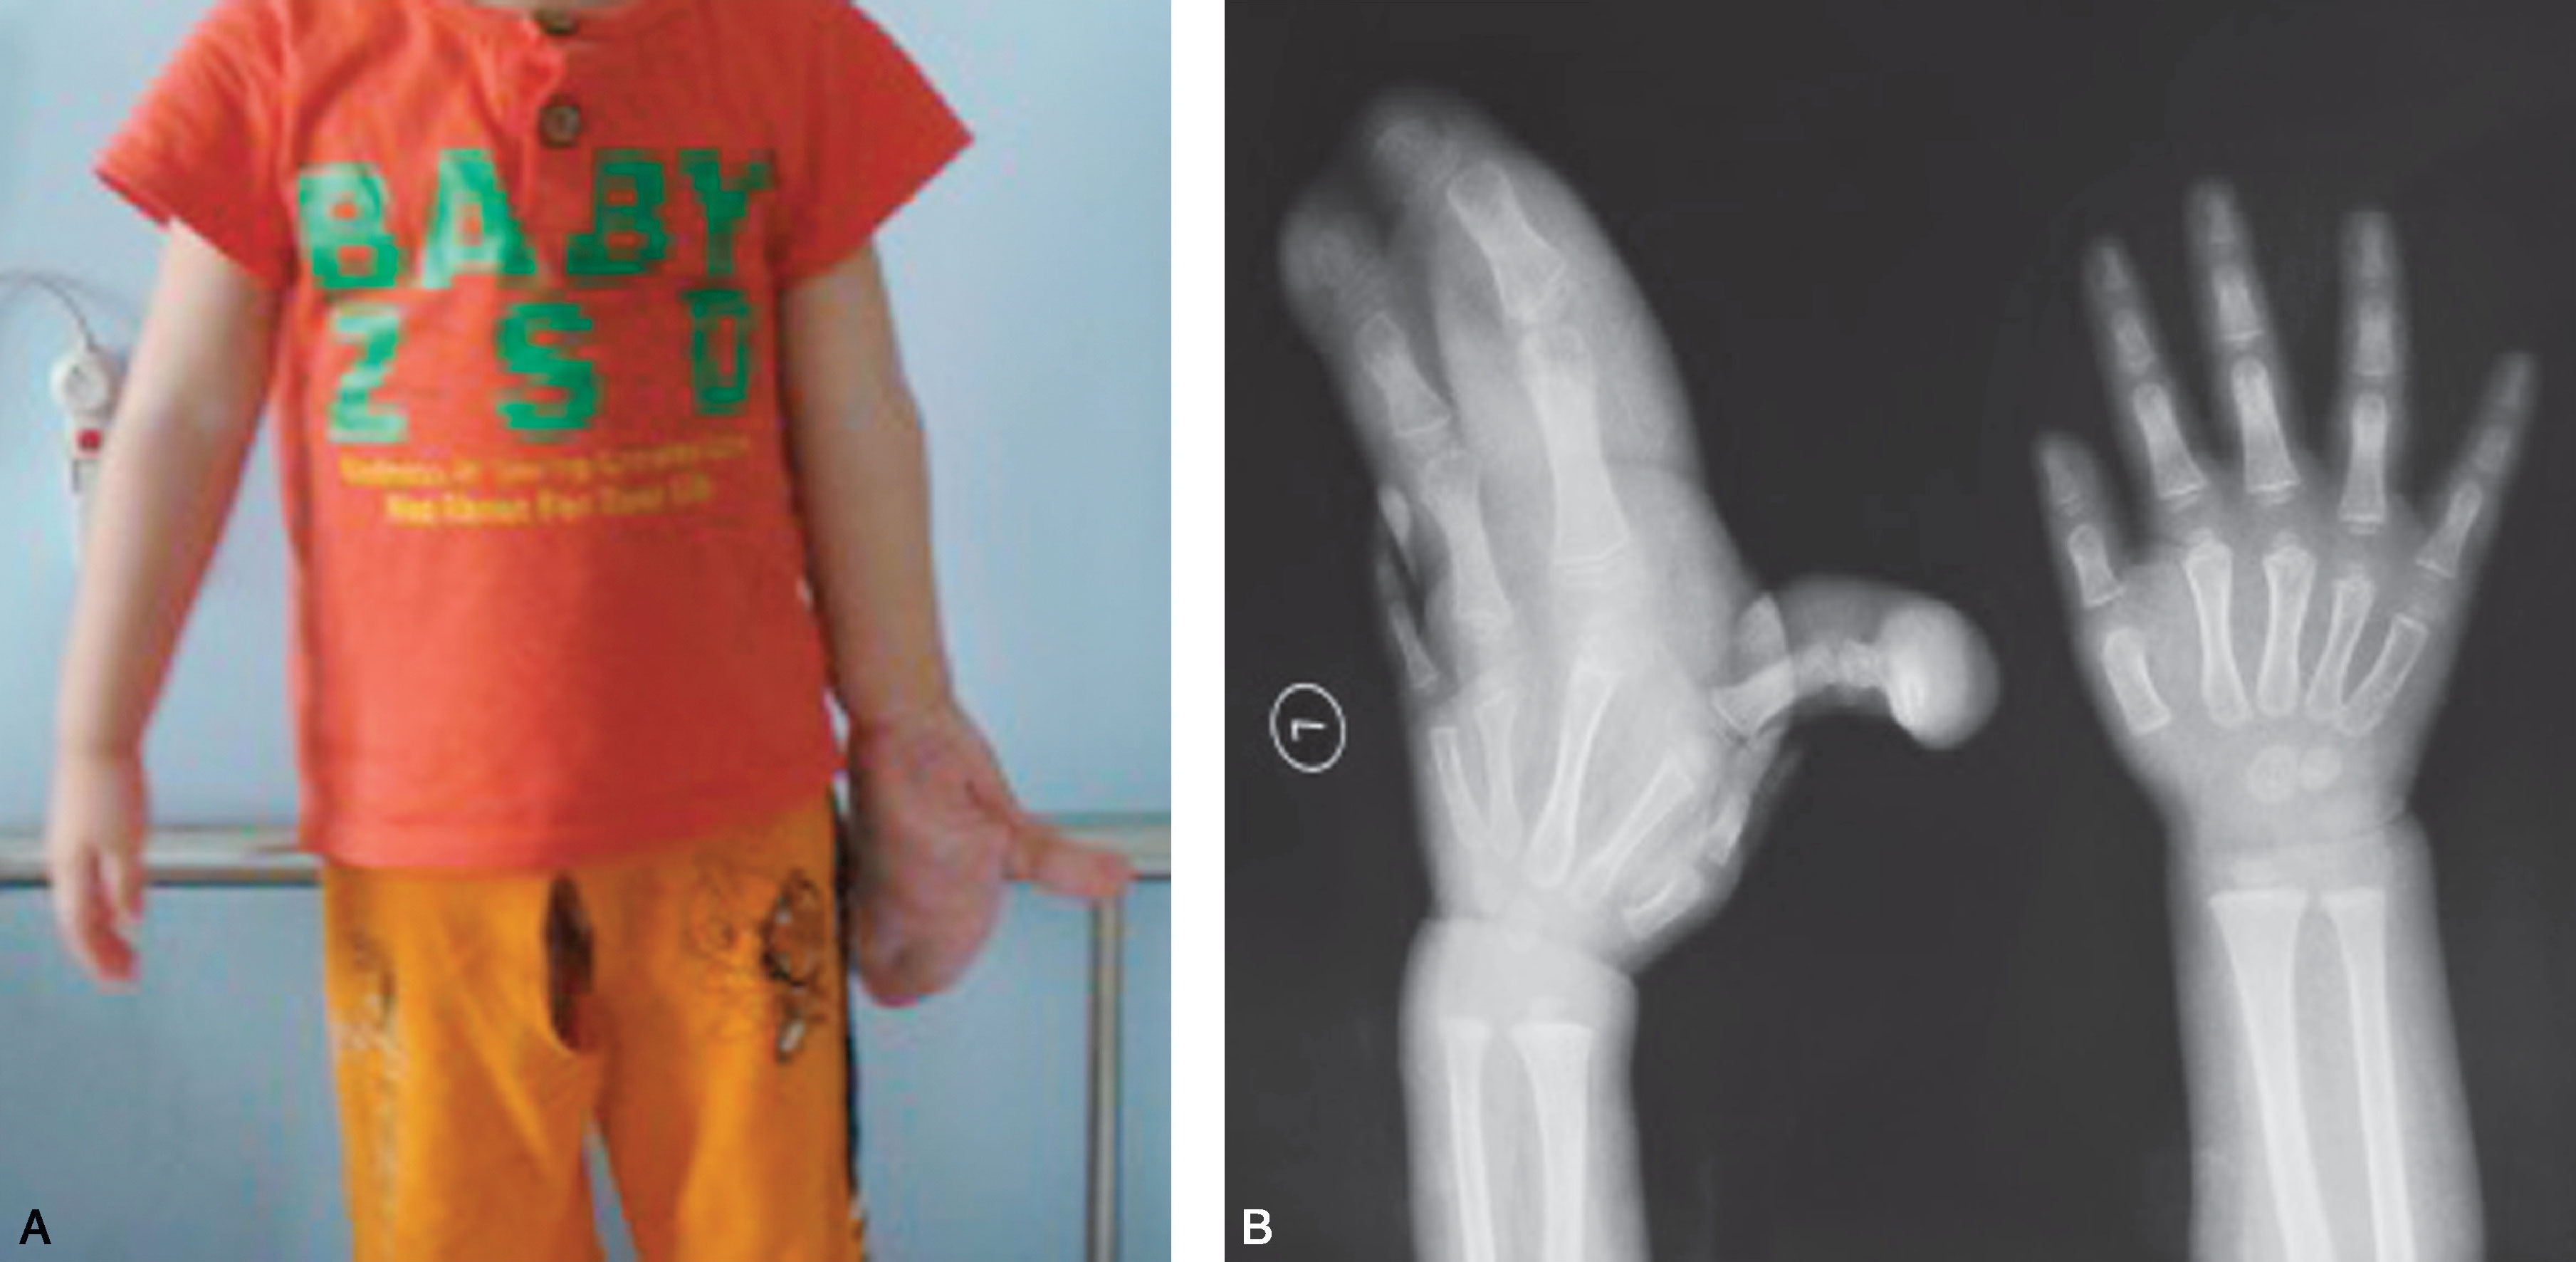

图1-2-4 桡骨部分缺如病例

X 线片显示右侧桡骨远端部分缺如,尺骨短粗,拇指漂浮拇

图1-2-5 桡骨完全缺如病例

A.右侧前臂桡侧纵列发育不良,拇指完全缺如;B.X 线片显示桡骨完全缺如,腕关节极度桡偏、脱位